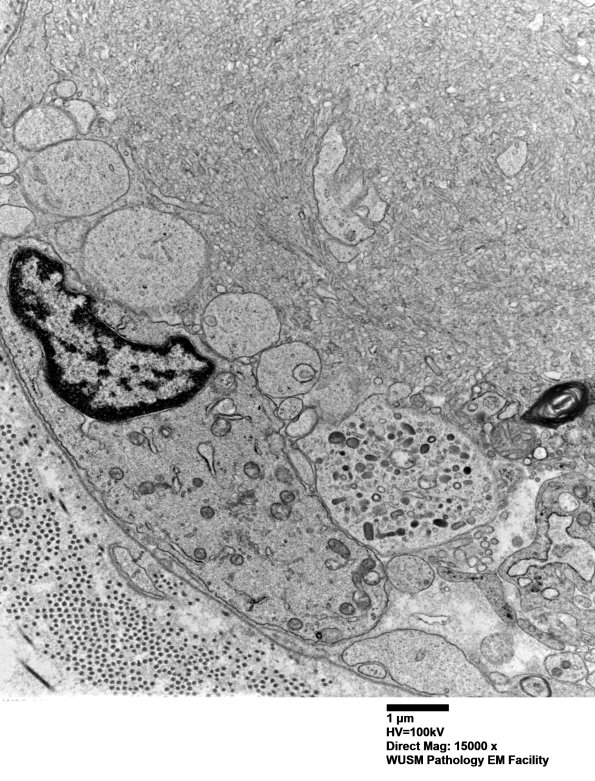

Higher magnification of image #16C5. (electron micrograph)

Washington University Experience | PERIPHERAL NEUROPATHY | 19 TRAUMATIC INJURIES | 16C6 (Case 16) L PIN nerve_027 - Copy